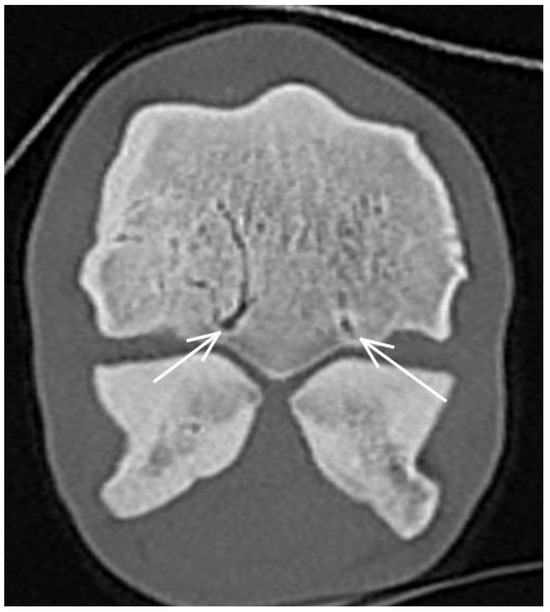

3.3. The Proximal Sesamoid Bones (PSBs)

| Proximal sesamoid bone Medial/Lateral | |||

| Prominent vascular channels Thickening of axial/abaxial compact bone Increased attenuation in trabecular bone Modelling | Thickening of axial/abaxial compact bone Decreased signal intensity in trabecular bone Modelling | Prominent vascular channels Modelling | |